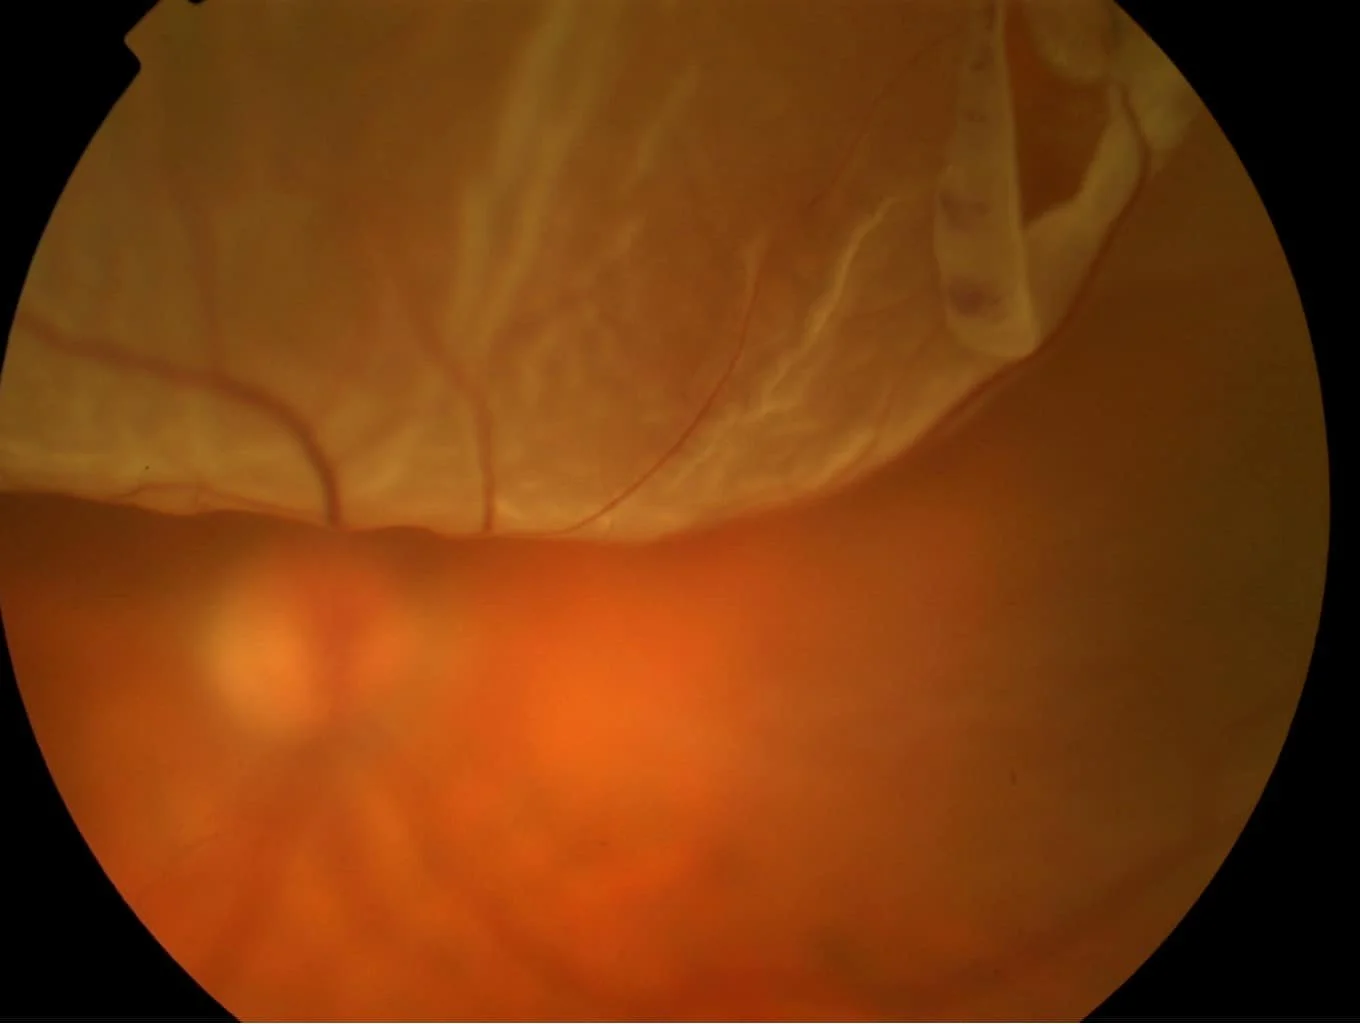

Αποκόλληση αμφιβληστροειδούς - συμπτώματα, διάγνωση & αντιμετώπιση

O πιο συχνός τύπος, που οφείλεται σε ρωγμή ή οπή στον αμφιβληστροειδή. Συνδέεται συχνά με υψηλή μυωπία ή αποκόλληση υαλοειδούς. Μέσα από τη ρωγμή περνά υγρό, το οποίο «σηκώνει» τον αμφιβληστροειδή.

Παρατηρείται κυρίως σε ασθενείς με προχωρημένη κατά κύριο λόγο διαβητική αμφιβληστροειδοπάθεια. Οι νέες παθολογικές μεμβράνες «τραβούν» σταδιακά και μηχανικά τον αμφιβληστροειδή προς τα εμπρός, δημιουργώντας αποκόλληση.